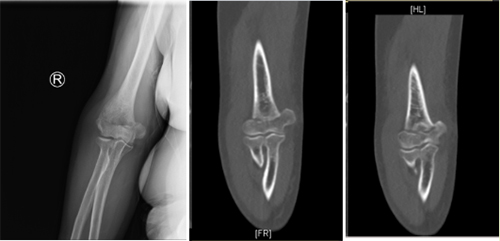

家住德州市的李大娘今年76岁,因大雪摔倒导致右肘部疼痛,当地医院拍X线显示右侧肱骨远端粉碎性骨折,考虑到李大娘是高龄患者,且合并高血压、糖尿病、冠心病等基础疾病,遂转来我院创伤中心进行治疗。在麻醉手术科的默契配合下,创伤中心医师仅耗时1小时便完成手术。术中透视显示骨折解剖复位,内固定位置好,术后第二天,李大娘就在科室康复师的帮助下开始锻炼。